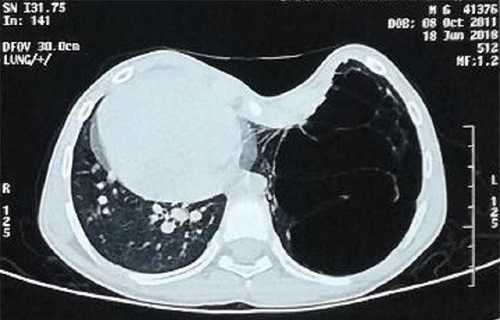

Bé trai 7 tuổi mang trong người hai dị tật hiếm gặp khiến bé luôn khó thở, tức ngực, nếu không can thiệp sớm có thể nguy hiểm đến tính mạng.